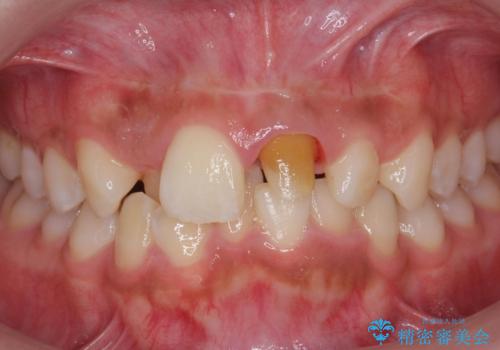

前歯の見た目が気になる。

- 前歯の見た目が気になるとの事で来院。

根の治療のやりかえは希望されなかったので土台だけやりかえを行い、ジルコニアクラウンで治療を行いました。

綺麗な被せ物が入り大変満足して頂けました。